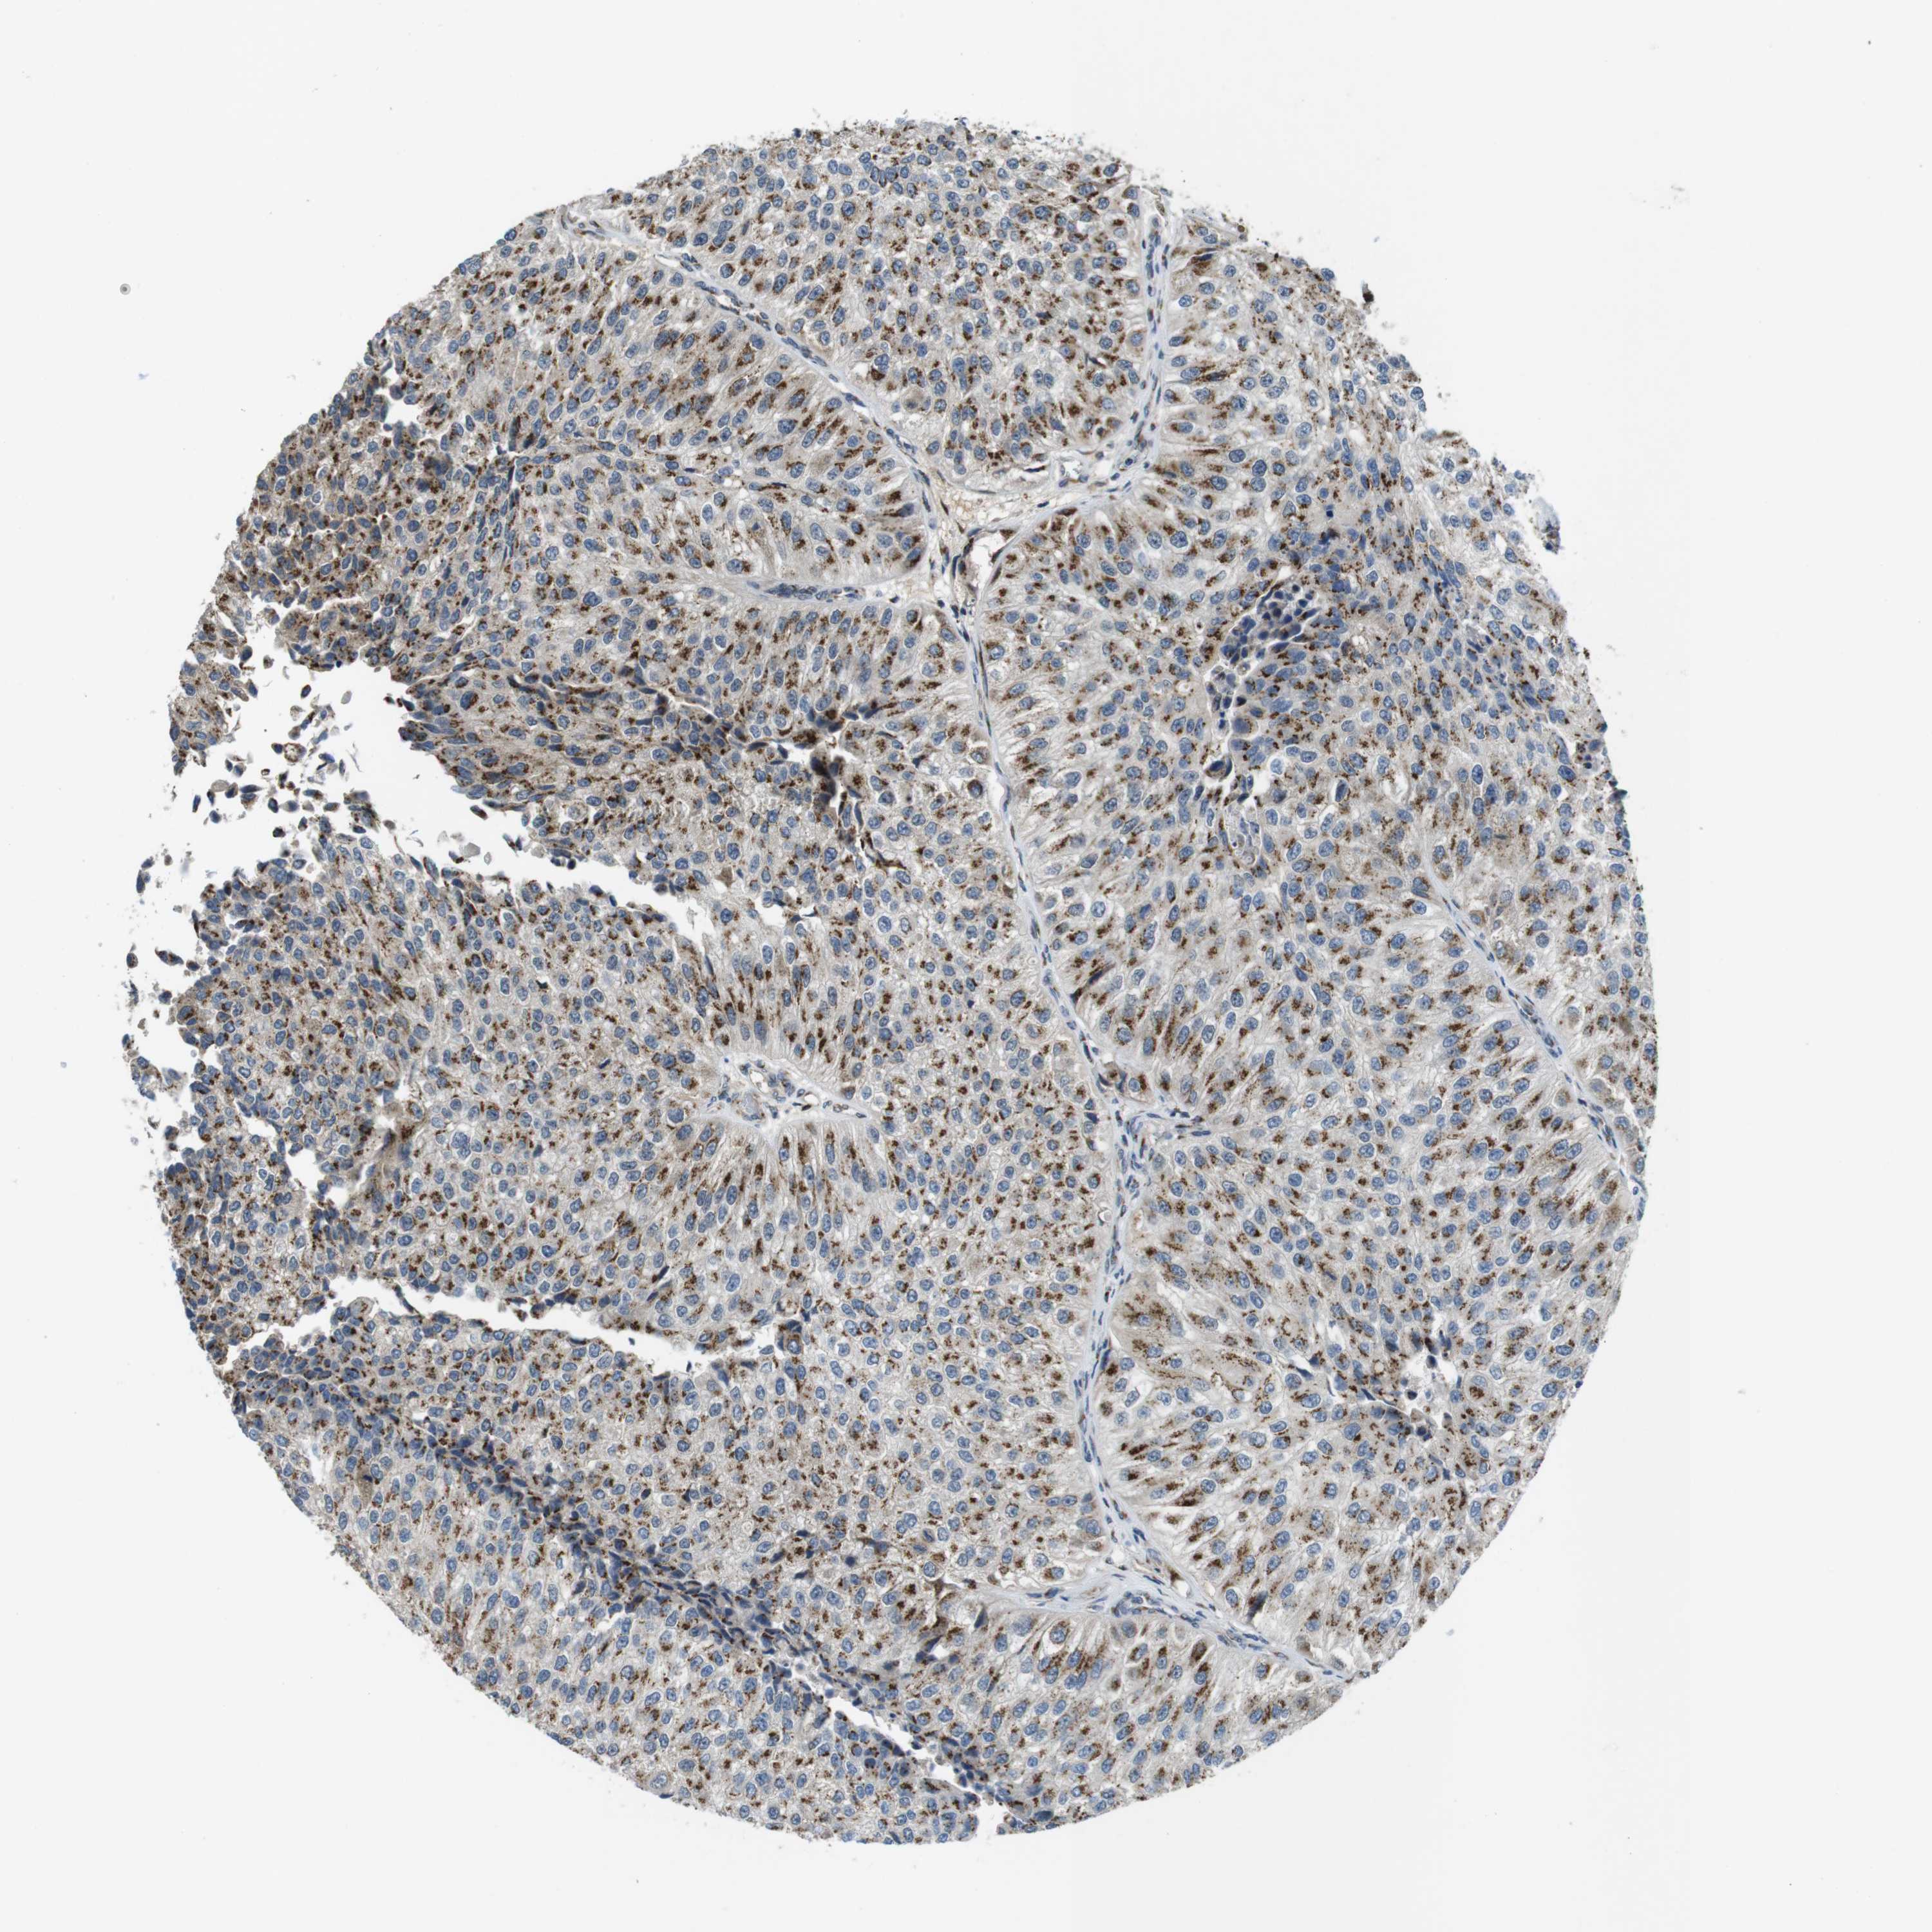

UROTHELIAL CANCER - Protein expressioni

A mouse-over function shows sample information and annotation data. Click on an image to view it in a full screen mode. Samples can be filtered based on level of antibody staining by selecting one or several of the following categories: high, medium, low and not detected. The assay and annotation is described here.

Note that samples used for immunohistochemistry by the Human Protein Atlas do not correspond to samples in the TCGA dataset.

Antibody stainingi

Antibody staining in the annotated cell types in the current human tissue is reported as not detected, low, medium, or high, based on conventional immunohistochemistry profiling in selected tissues. This score is based on the combination of the staining intensity and fraction of stained cells.

Each image is clickable and will lead to virtual microscopy that enables deeper exploration of all samples and also displays staining intensity scores, fraction scores and subcellular localization as well as patient and tissue information for each sample.

Antibody HPA014909

Antibody HPA017347

Staining

High

Medium

Low

Not detected

Intensity

Strong

Moderate

Weak

Negative

Quantity

>75%

75%-25%

<25%

None

Location

Nuclear

Cytoplasmic/membranous

Cytoplasmic/membranous,nuclear

Urothelial carcinoma, Low grade

Urothelial carcinoma, High grade